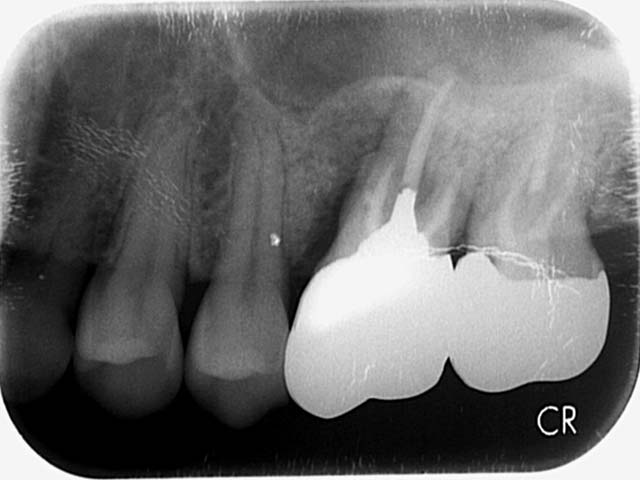

人工植牙 首頁 案例分享 人工植牙 前牙植牙 更多 牙橋嚴重蛀牙,即拔即種,避免二次傷口 更多 齒槽骨保存術+植牙 更多 前牙審美植牙 更多 微創植牙 更多 小臼齒植牙 更多 即拔即種 更多 鼻竇增高術(垂直)+植牙 更多 鼻竇增高術(側窗) 更多 «1»